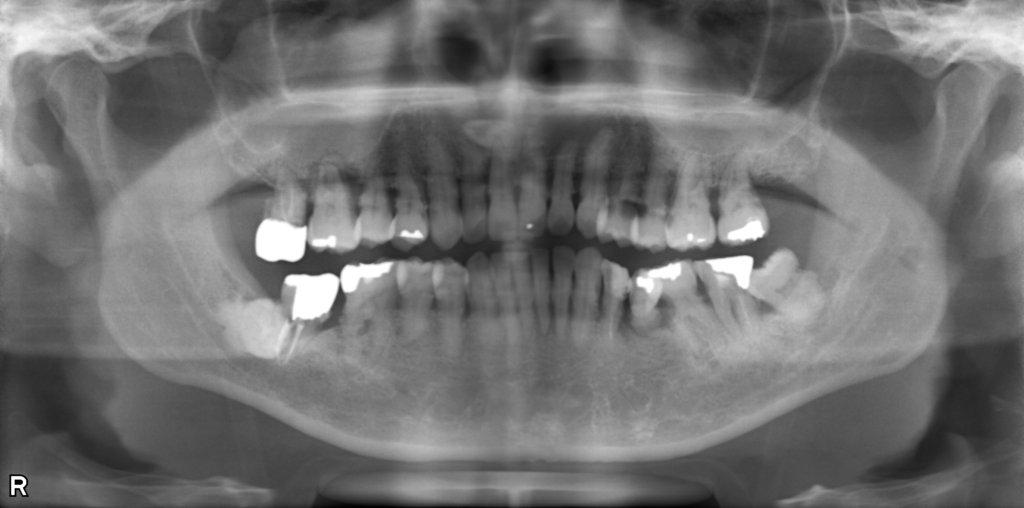

↑治療前後で骨の状態が改善しています。現在は隣の歯と固定して経過を見ています。

↑レントゲンで骨吸収を認めます。歯肉を切開すると実際に骨がありません。